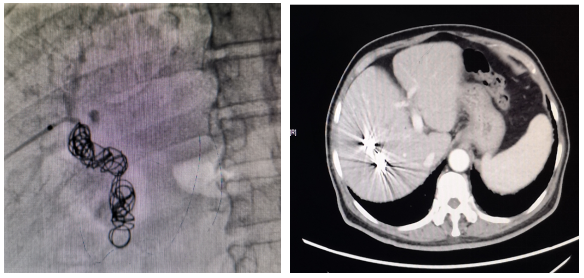

图示:PVE照片及PVE后8周肝脏增强CT

4. 疗效评估

患者肝脏储备功能不足,残肝体积过小,选择PVE进行转化。PVE等待肝脏增生期间,选择TKI仑伐替尼治疗控制肿瘤,最终转化成功,完成了右半肝切除,患者顺利出院。此例患者高龄,采用“PVE+TKI”的策略获得了手术机会,在手术安全性和肿瘤学上均取得满意